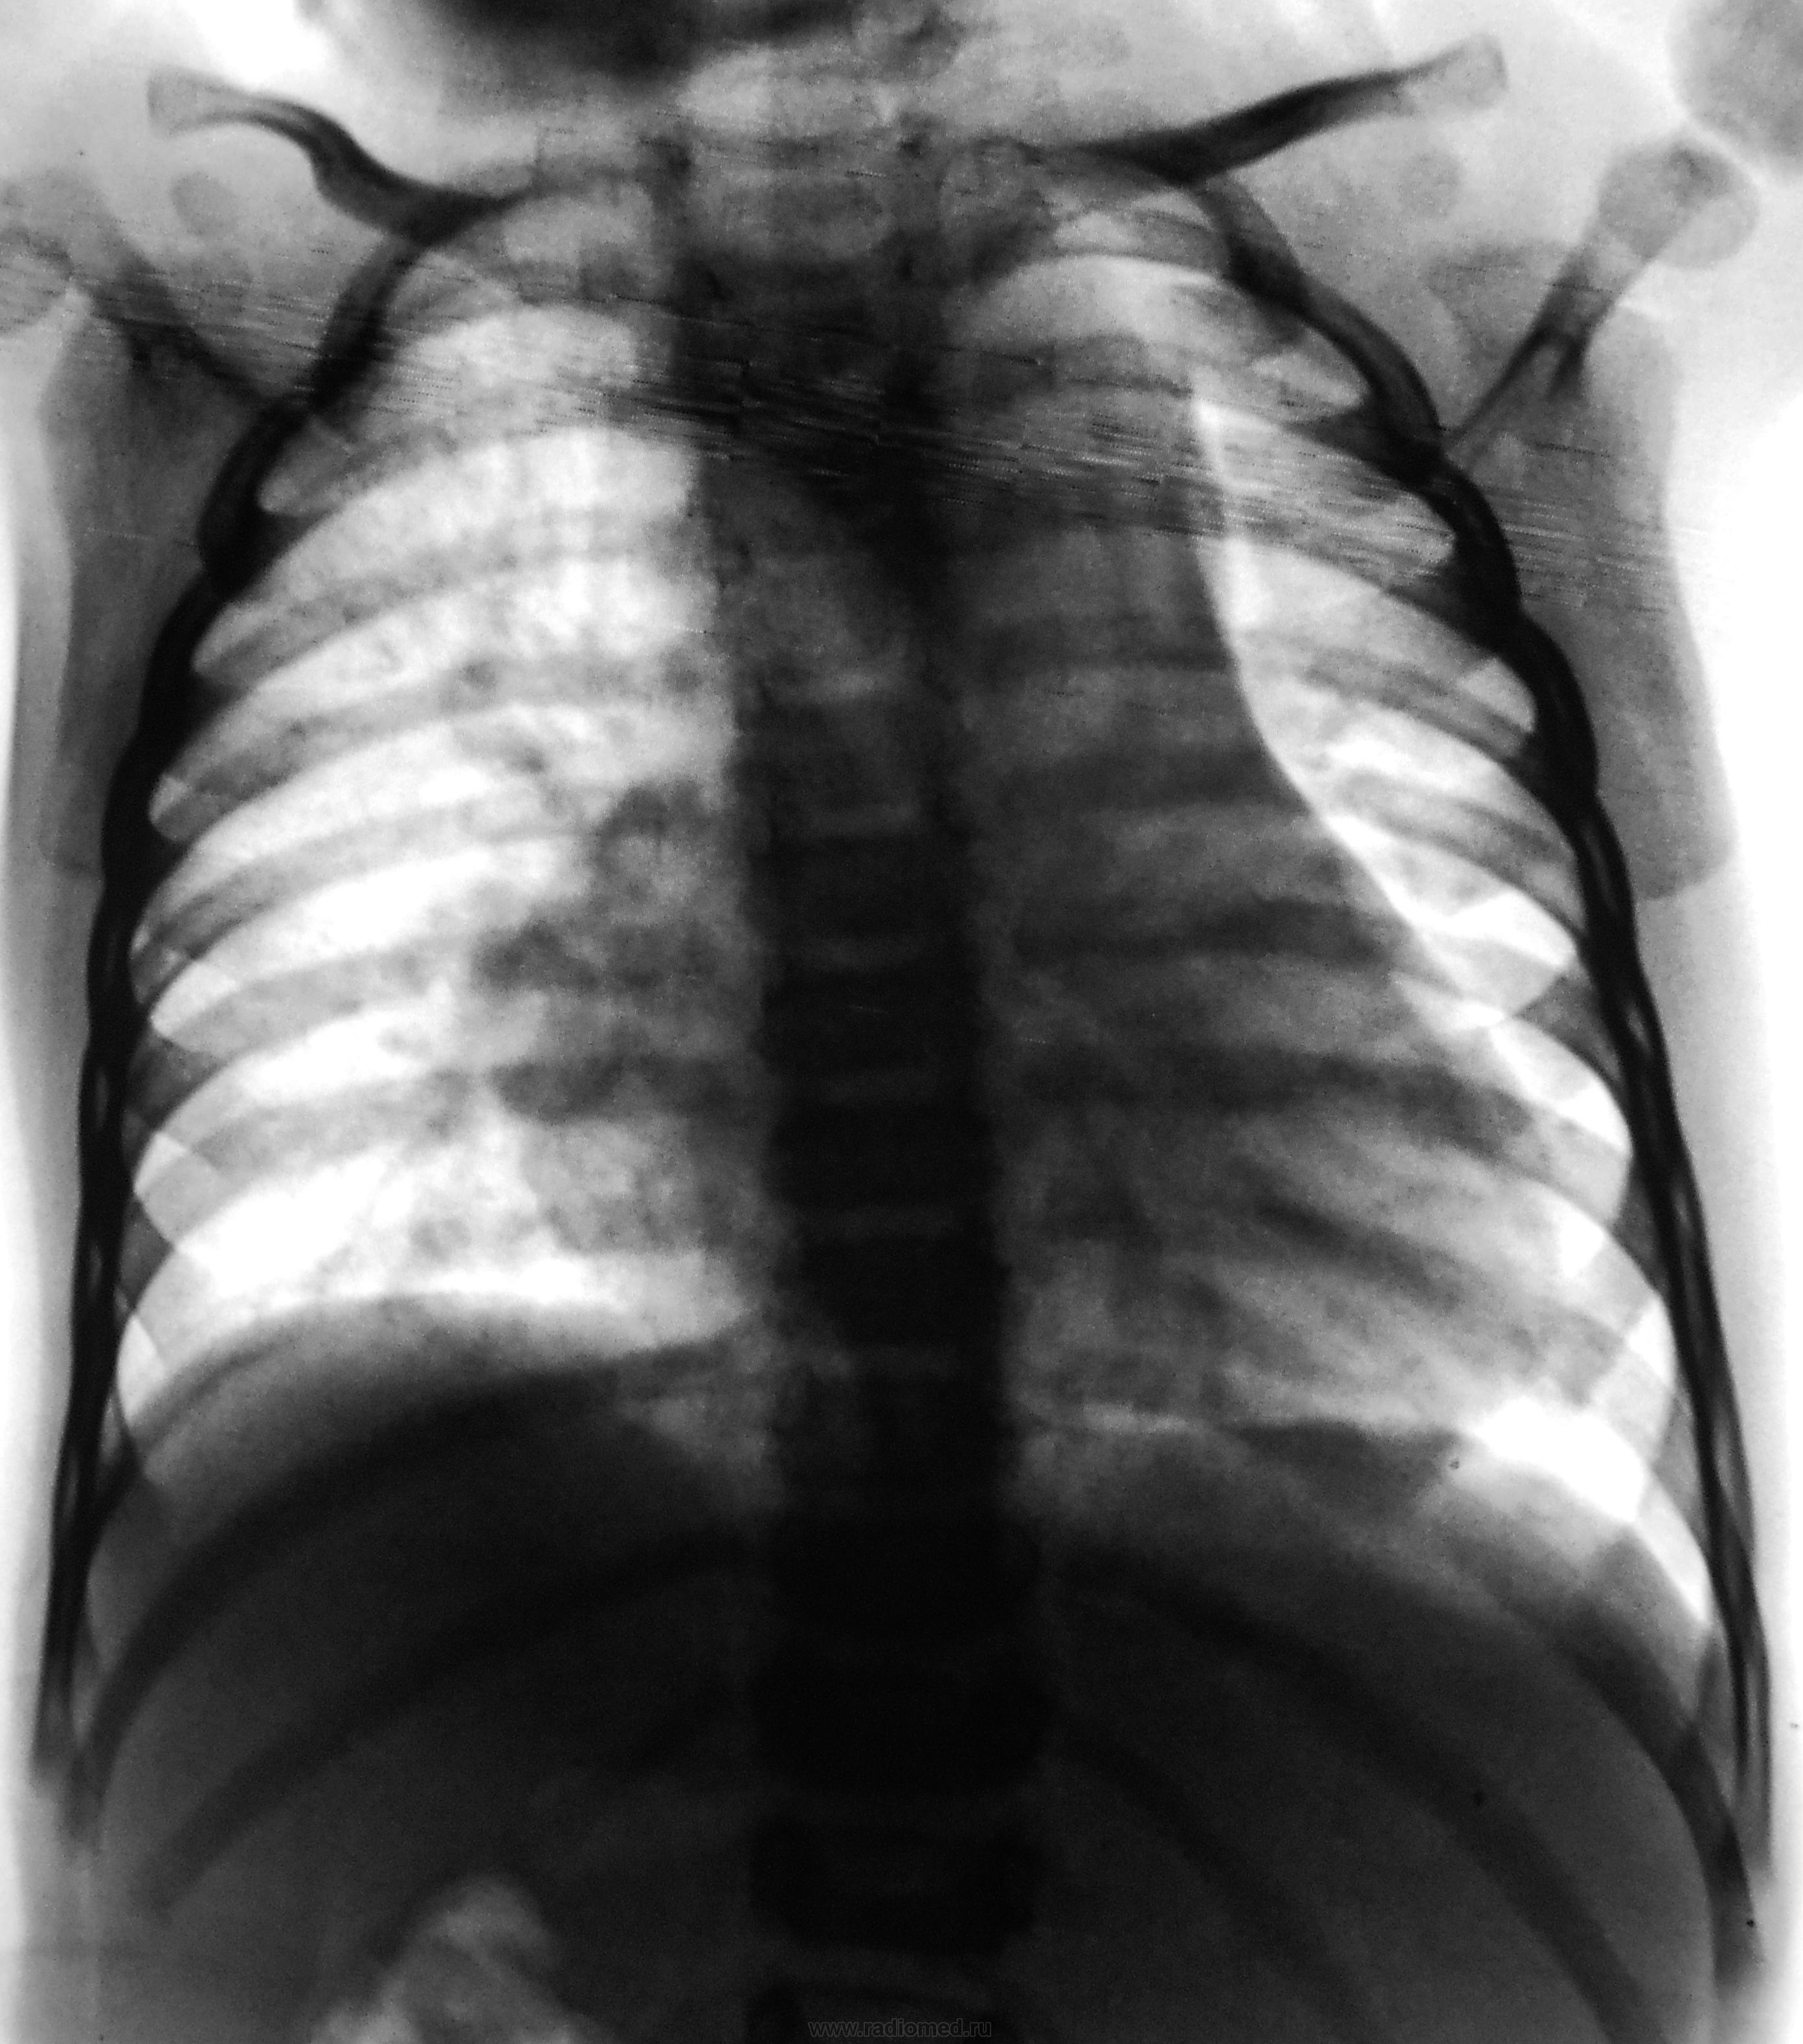

Пол пациента: Женский пол Тип патологии: Другое Область исследования: Грудная клетка и верхние дыхательные пути Методы исследования: Rg Пациент направлен на рентгенографию ОГК с диагнозом - "врожденный порок" https://radiomed.ru/sites/default/files/styles/case_slider_image/public/user/12/2.dscn0454a.jpg?itok=NsBvrkBp https://radiomed.ru/sites/default/files/styles/case_slider_image/public/user/12/3.dscn0455.jpg?itok=JbtadSKP ID:24004 Пнд, 29/10/2012 - 19:49 #1 И.Бондаренко Не на сайте Был на сайте: 1 день 22 часа назад Зарегистрирован: 13.09.2011 - 22:55 Публикации: 9206 Какой возраст "врожденного порока"? Пнд, 29/10/2012 - 20:10 #2 Катенёв Валенти... Не на сайте Был на сайте: 7 лет 2 недели назад Зарегистрирован: 22.03.2008 - 22:15 Публикации: 54876 1 год и 4 месяца. Пнд, 29/10/2012 - 21:23 #3 Dr.Yllich Не на сайте Был на сайте: 1 год 4 месяцев назад Зарегистрирован: 01.05.2011 - 22:52 Публикации: 1196 Размеры и форма сердечной тени "годятся" для врожденного порока, но ЭХО-кардиография обладает гораздо большими возможностями в этих вопросах, чем обзорная рентгенография. С уважением. Ильич. Втр, 30/10/2012 - 17:02 #4 Santuus Не на сайте Был на сайте: 2 года 5 месяцев назад Зарегистрирован: 01.07.2009 - 23:08 Публикации: 109 Согласен с доктором Dr.Yllich

1 год и 4 месяца.

Размеры и форма сердечной тени "годятся" для врожденного порока, но ЭХО-кардиография обладает гораздо большими возможностями в этих вопросах, чем обзорная рентгенография.